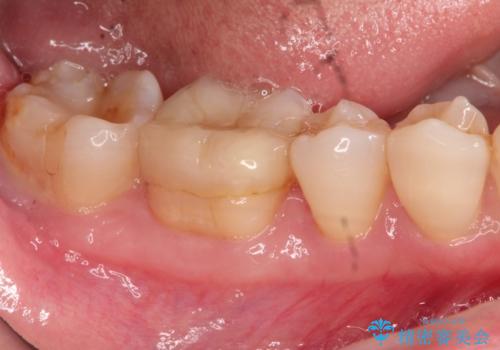

- 以前治療した右下の奥歯の歯の中が虫歯になっている気がするとのことで来院されました。

レントゲン上と視診上では確認できなかったのですが、患者様の希望もあり、一度かぶせ物を外して内部を確認し、オールセラミックを再度装着する計画としました。

やはり内部では少量の虫歯がありましたので、拡大鏡使用して虫歯を除去しました。